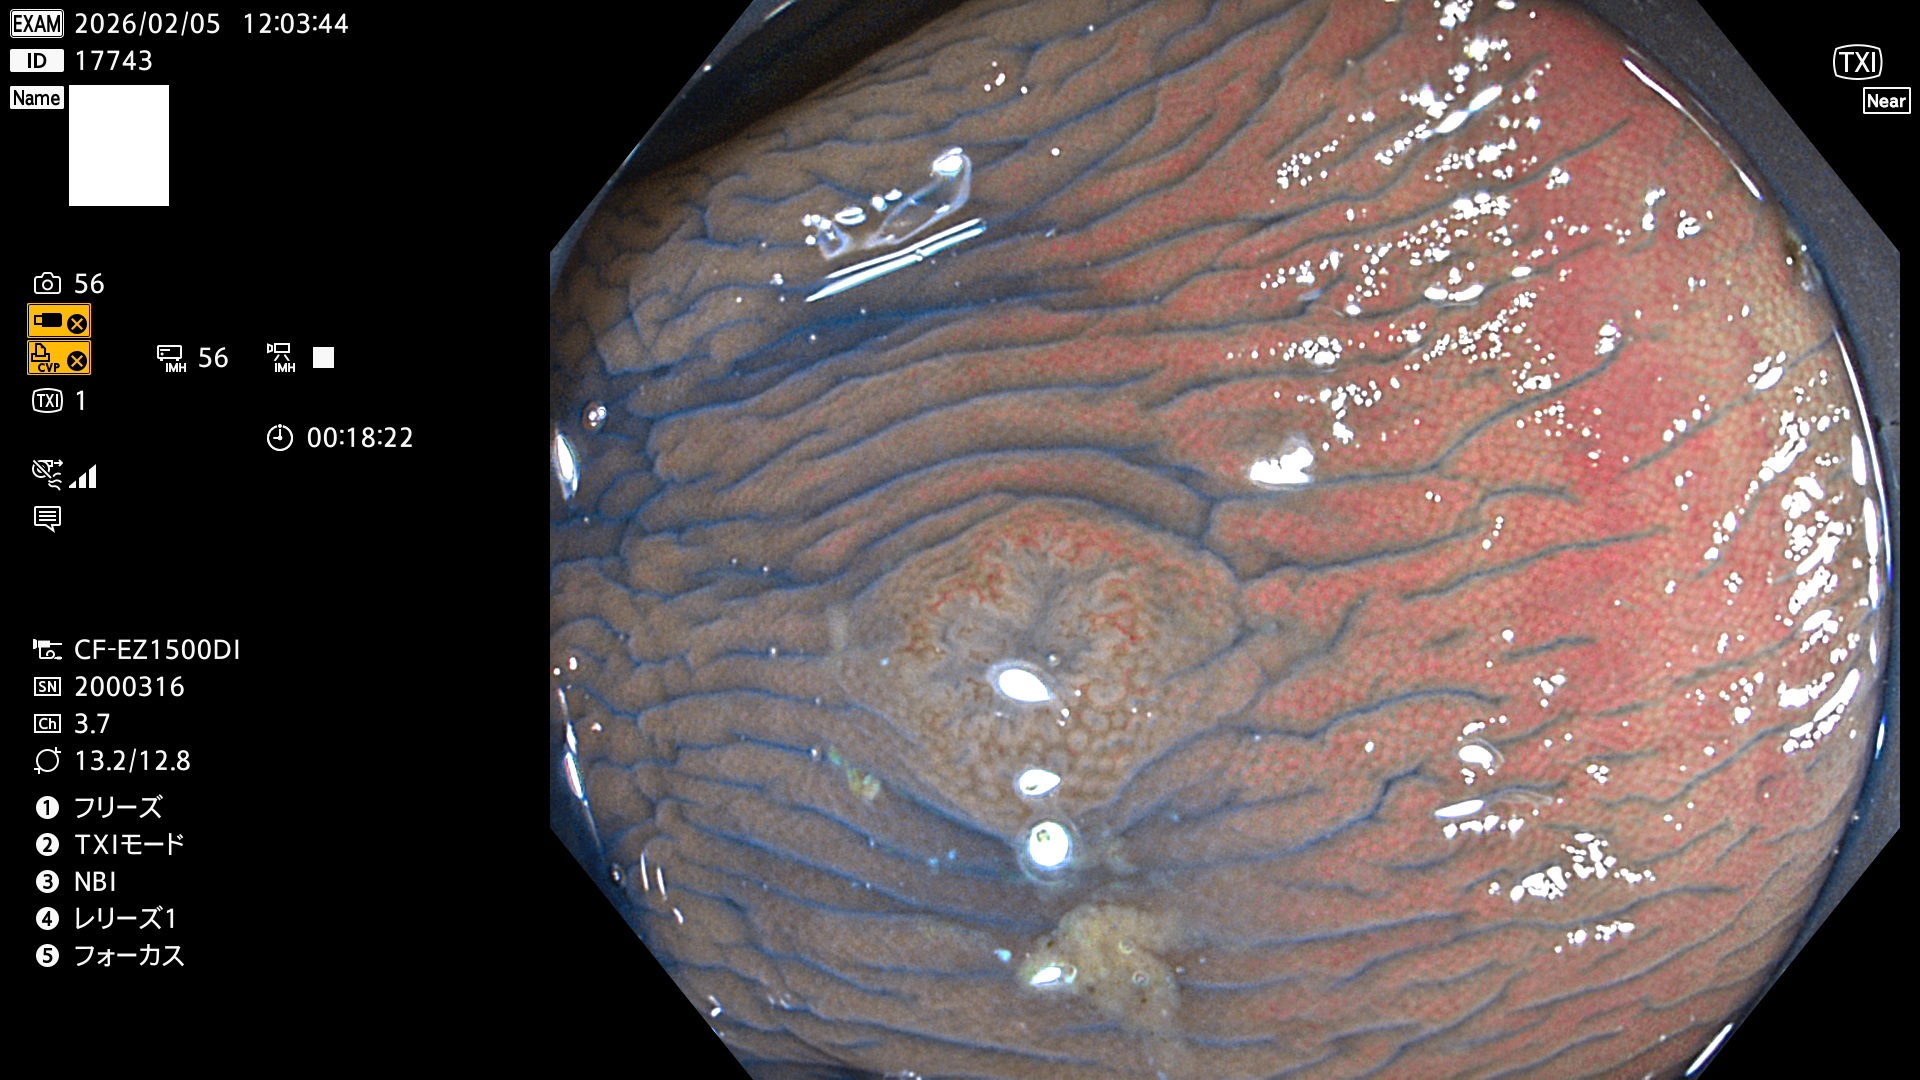

完全に平坦な物をUb、陥凹している物をUcと呼びます。Ubは認識が困難で、Ucはびらん(炎症)と紛らわしいために見落とされやすく、「内視鏡後・大腸癌」の原因になります。

専門的)Uc=De Novo癌? 内視鏡の解像度が低かった時代、このような説もありました。しかし今日の高精度内視鏡では良性の微小なUc型腺腫(APC遺伝子異常の腺腫)が日常的に見つかります。Ucこそが多段階発癌(Adenoma-Carcinoma Sequence)のMain Routeです。

毎週の検査(木・金・土・日)に発見されたUbとUc型・腺腫を、その週の日曜の夜にUPし1週間、提示します。

2026年2月5日〜2月8日の4日間(40件)で9個 (Uc_ADR=9個/40人=23%)